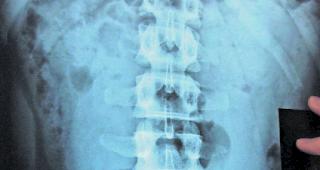

Beweismittel. Die Röntgenaufnahme zeigt mehrere der Fingerlinge im Darm eines Bodypackers.

Drogenschmuggel | Im Oberwallis wird jeden...

Drogenkuriere mit vollem Magen

Walliser Bote | Oberwallis. Was viele aus Hollywoodverfilmungen über kolumbianische Drogenkartelle kennen, gehört [...]

Grenzwacht. Bei den Bodypackern ist ohne medizinische Untersuchung nichts zu finden.

Oberwallis | Bodypacker verstecken...

Drogenschmuggel im Körper

Walliser Bote | Bereits sieben Bodypacker wurden in diesem Jahr im Oberwallis von der Kantonspolizei gefasst. Sie [...]